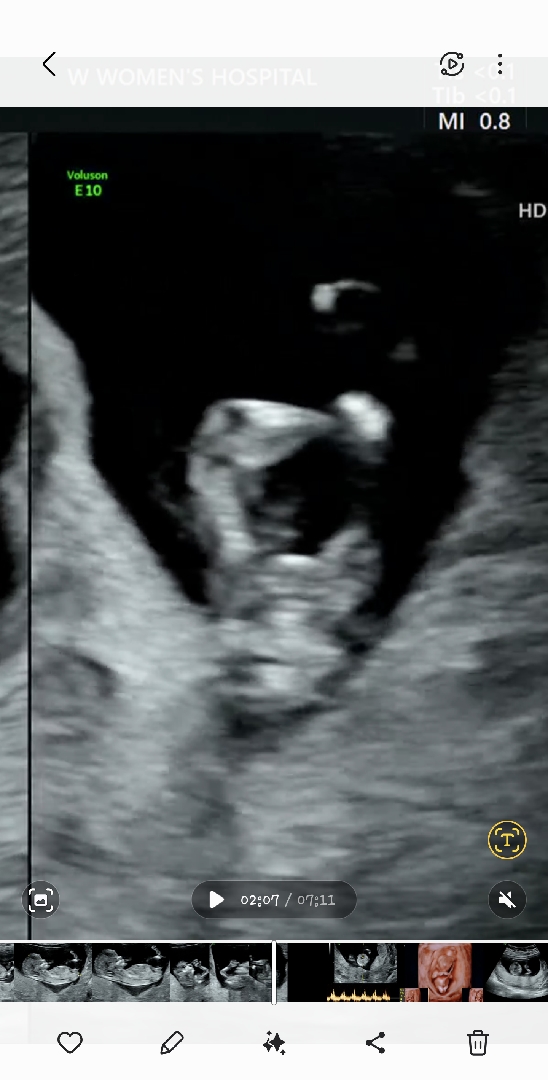

여기두번째사진이에용

각도법 봐주세요ㅠㅠ

성별 궁금해요!!